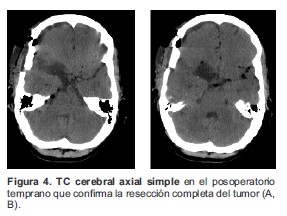

Paciente femenino de 21 años de edad, que acude a la consulta de neurocirugía con clínica de cefalea de 10 años de evolución, asociada a eventos de sincope en los últimos 2 años, los cuales se precedían de sensación de vértigo y parestesias generalizadas. Al interrogatorio no reveló antecedentes de importancia, el examen físico general y neurológico no evidenció anormalidad alguna. La evaluación con tomografía craneal (TC) simple presenta una lesión con densidad de grasa (hipodensa) en la cisterna silviana derecha asociada a otra lesión cálcica adyacente anterior (Figura 1). Se realiza resonancia magnética (RM) cerebral simple y contrastada evidenciándose en las imágenes simples, una masa hiperdensa extra axial, en cisterna silviana derecha, con bordes regulares, de aproximadamente 3.2x2.1cm de diámetro, asociado a pequeñas lesiones hiperintensas diseminadas en las cisternas de la base (Figura 2), en la imagen contrastada de T1 se ve una masa hipointensa que no capta el medio de contraste (Figura 3). Por los hallazgos imaginológicos descritos se consideró que se trataba de un quiste dermoide roto y se procedió a preparar la paciente para el manejo quirúrgico de la lesión. Se realiza craneotomía fronto-temporal derecha, bajo visión microscópica se procede a disecar el valle de Silvio, hasta encontrar la lesión tipo masa, capsular, de color amarillento, con grumos grasos a su alrededor y vellosidades en su interior, extra axial, creciendo en la base craneana media, adherida al nervio óptico derecho y la arteria carótida interna derecha, se procede a realiza escisión completa de la lesión incluyendo la cápsula. Se realiza TC simple en el posoperatorio temprano en la cual se confirma la resección completa de la lesión (Figura 4). El informe de patología posteriormente confirmaría el diagnóstico de quiste dermoide. El egreso hospitalario se dio 3 días después del procedimiento quirúrgico sin complicaciones.

Figura 4. TC cerebral axial simple en el posoperatorio temprano que confirma la resección completa del tumor (A, B).